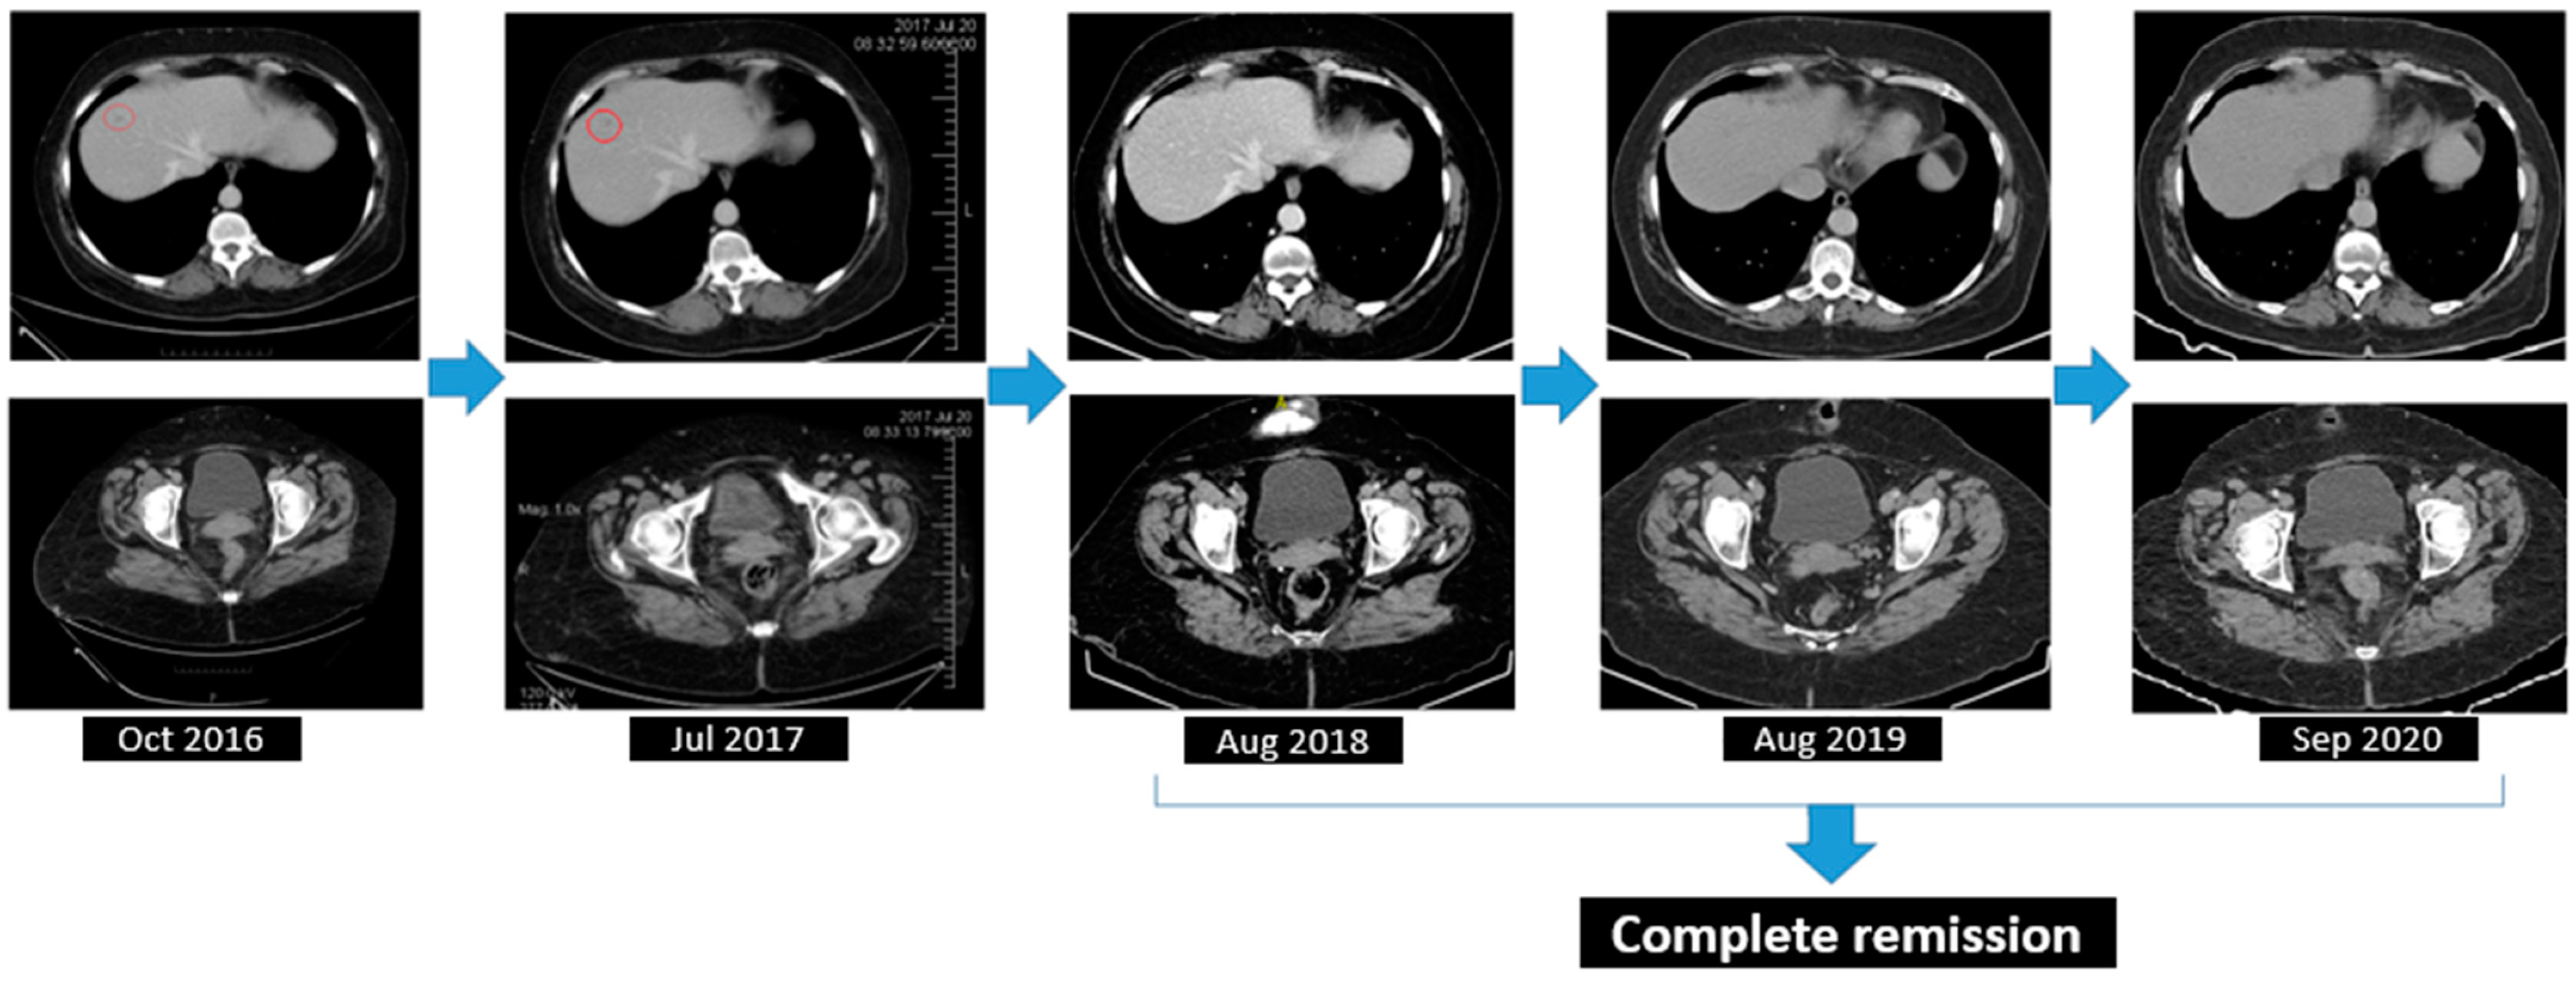

A significant result within the clinical narrative of this case, the detection of deleterious BRCA1 missense alterations in a compound heterozygous state, c.181T>G (p.Cys61Gly), in September 2016, set the stage for the introduction of Olaparib the following month. The therapeutic efficacy was confirmed via biannual CT scans of the thorax, abdomen, and pelvis, which indicated a positive outcome, achieving complete remission of the disease (Figure 9).

Figure 9.

Complete response assessed through CT from August 2018 to September 2020.

The longevity of the second patient’s survival post-diagnosis, now extending to 100 months, marks a significant success in the treatment of ovarian cancer. Notably, a remarkable PFS of 65 months was achieved under Olaparib treatment. This PFS aligns with the growing body of evidence supporting the efficacy of PARP inhibitors in extending survival rates. The complete radiological remission maintained from August 2018 to February 2022 underlines the potential of the use of Olaparib as a maintenance therapy, which has redefined the paradigms of survivorship in ovarian cancer and represents a testament to the enduring potential of personalized oncology treatment offered by PARP inhibitors. This milestone prompted clinical deliberation regarding the duration of maintenance treatment with Olaparib, especially in the context of the patient maintaining complete remission, given the low risk of myelodysplastic syndrome and acute myeloid leukemia as a side effect of PARP inhibitors. Are patients with no evidence of disease still gaining benefit from Olaparib treatment in this setting? Further studies might investigate the optimal duration of the treatment due to well-known acquired resistance mechanisms.